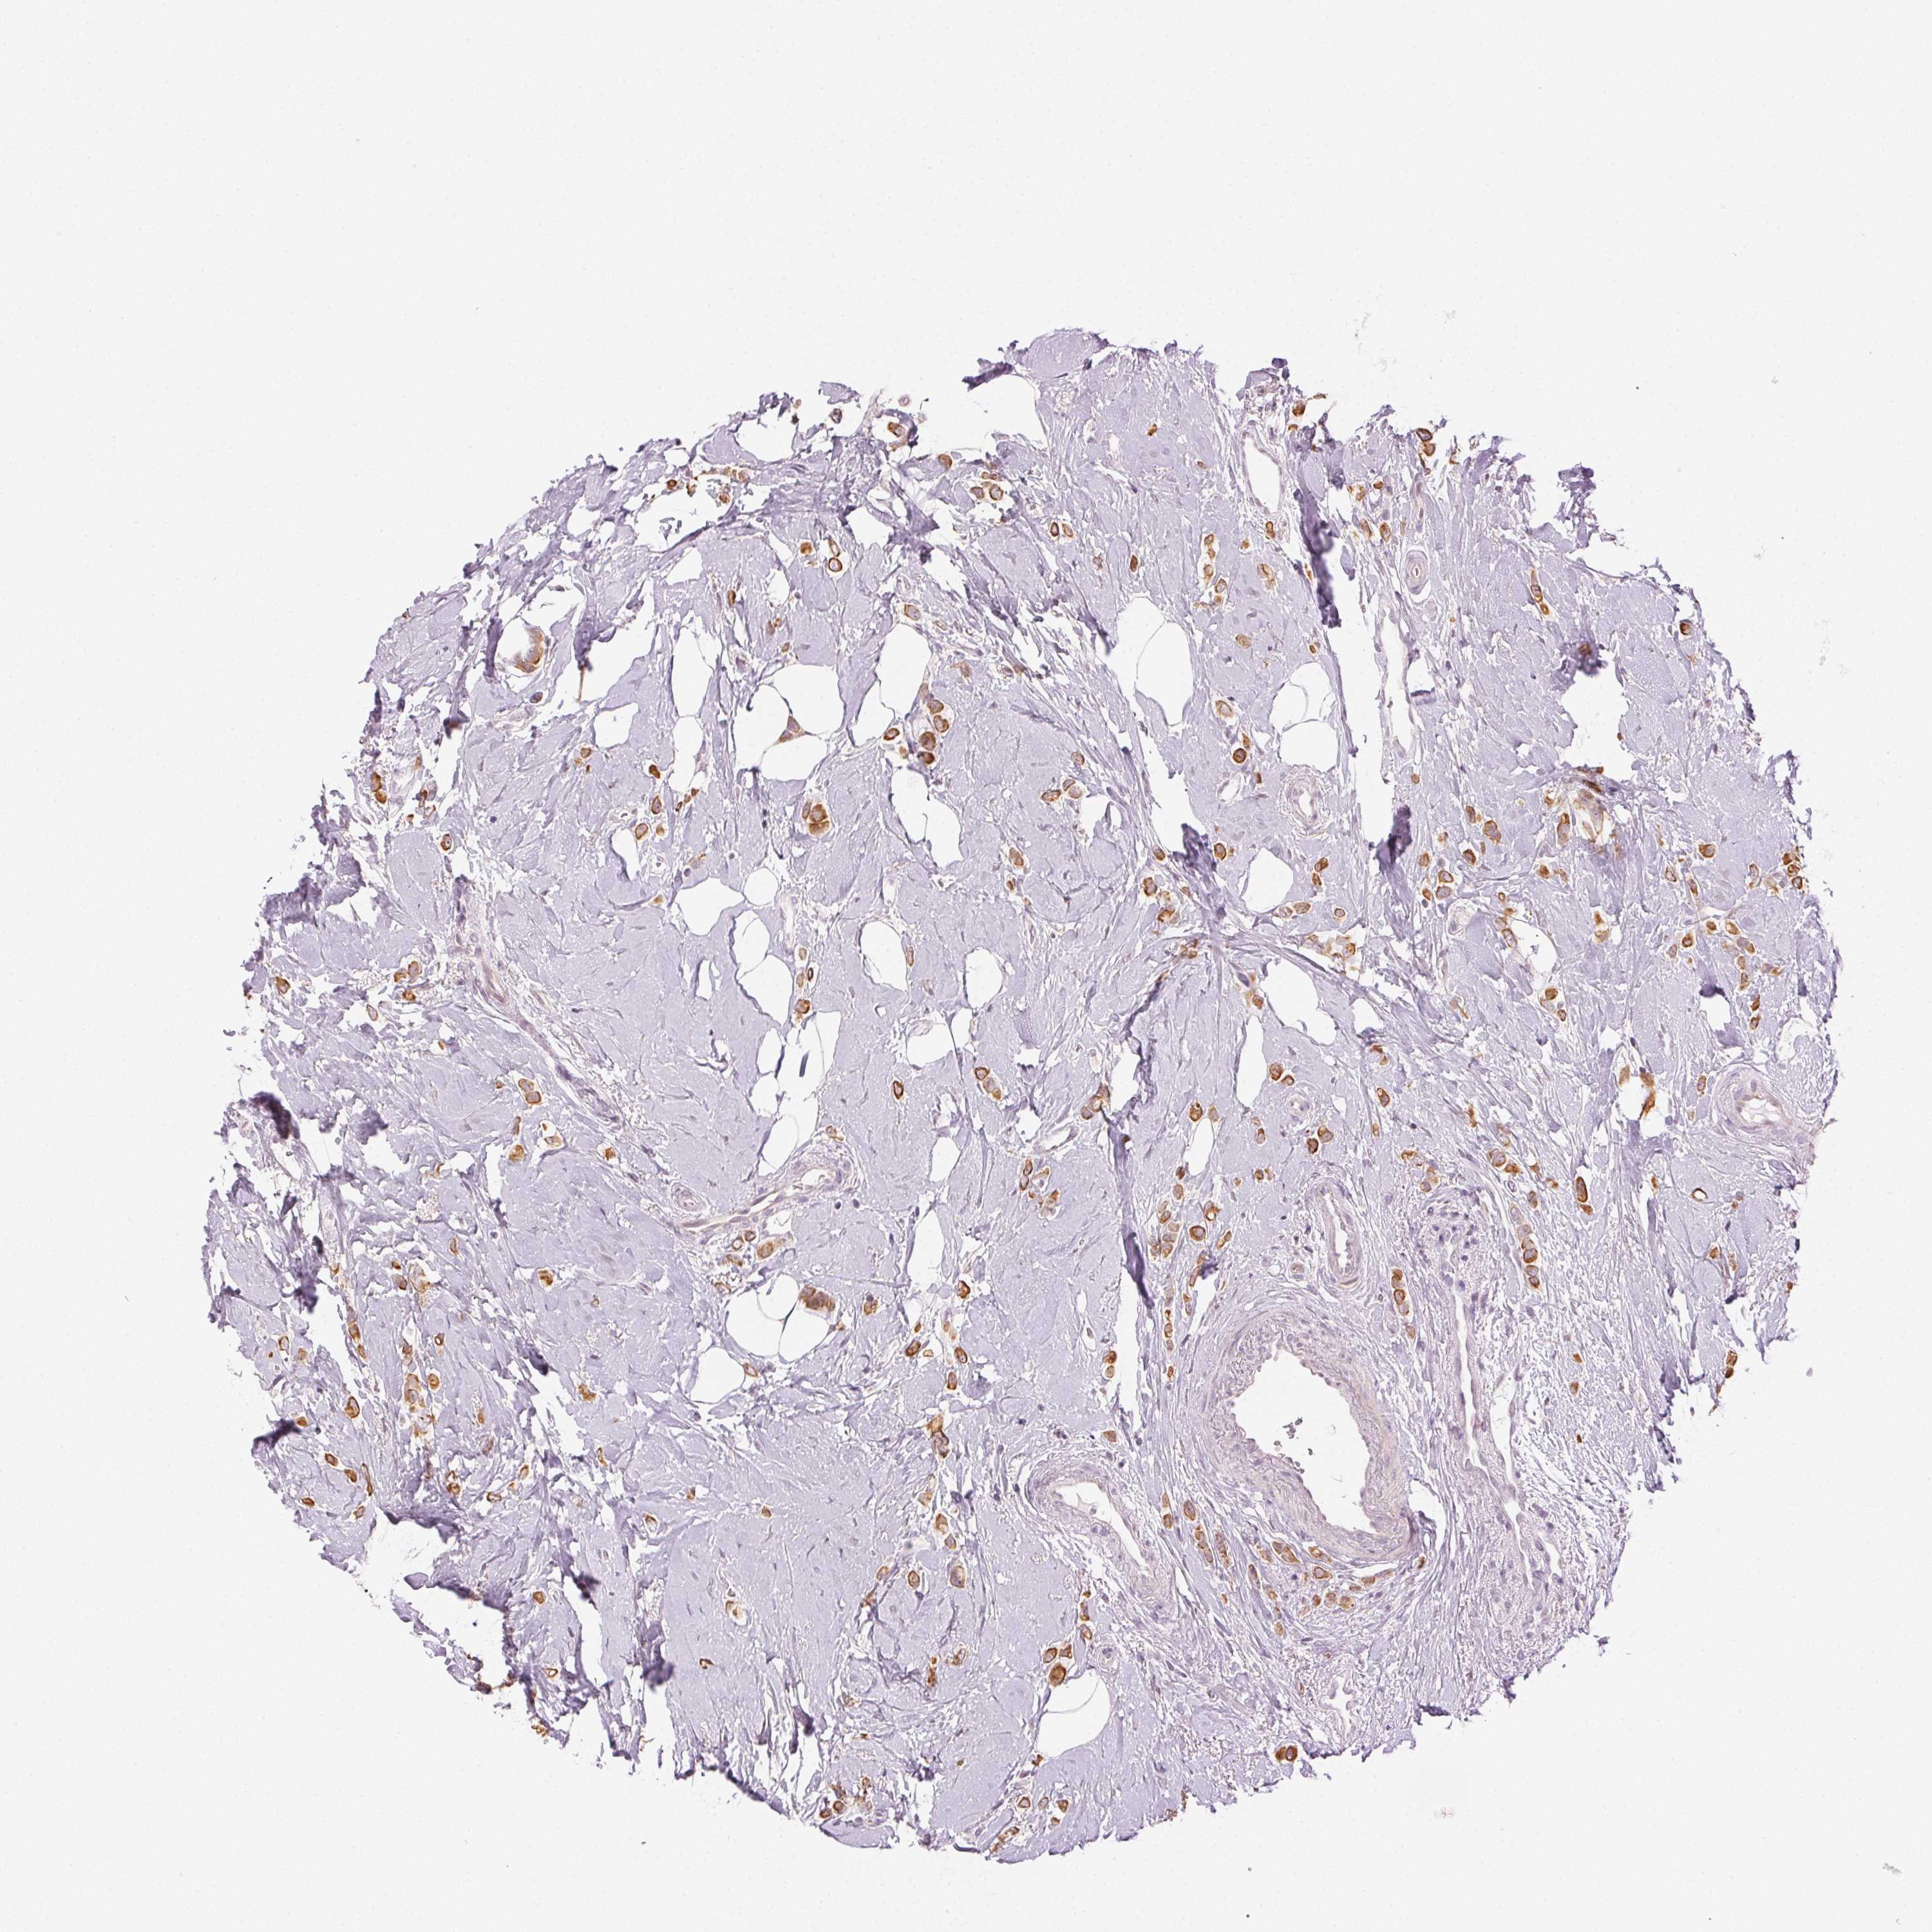

BRCA TCGA BRCA VALIDATION PROTEIN EXPRESSION